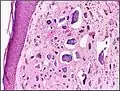

Micrograph of calcinosis cutis. The calcification is purple (bottom of image). H&E stain.